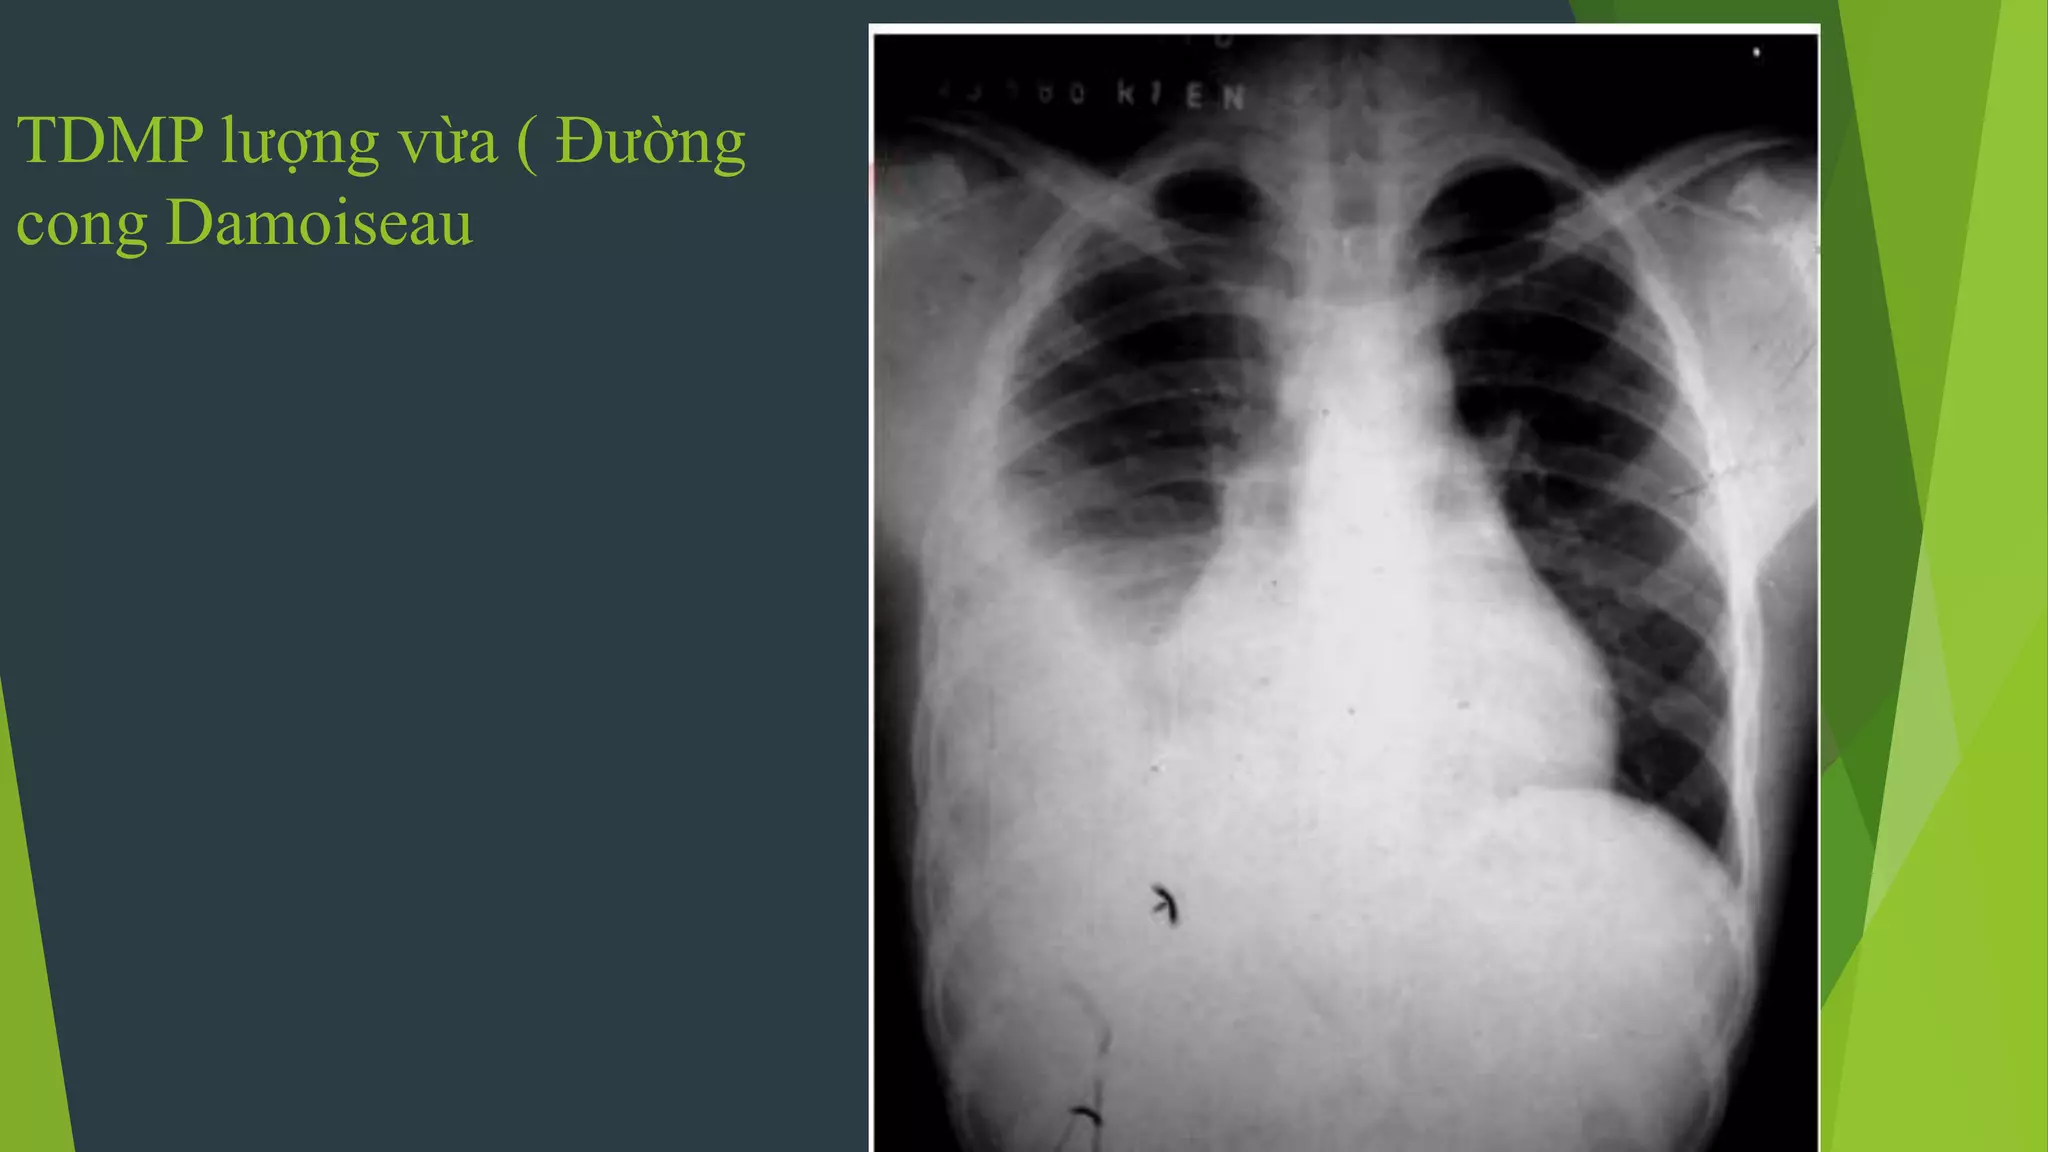

TDMP lượng vừa ( Đường

cong Damoiseau

Tràn dịch màng phổi tự do

 Hình ảnh mờ đậm thuần

nhất , không có hình ảnh

nhu mô phổi.

 Mất góc sườn hoành

 Có đường cong Damoiseau